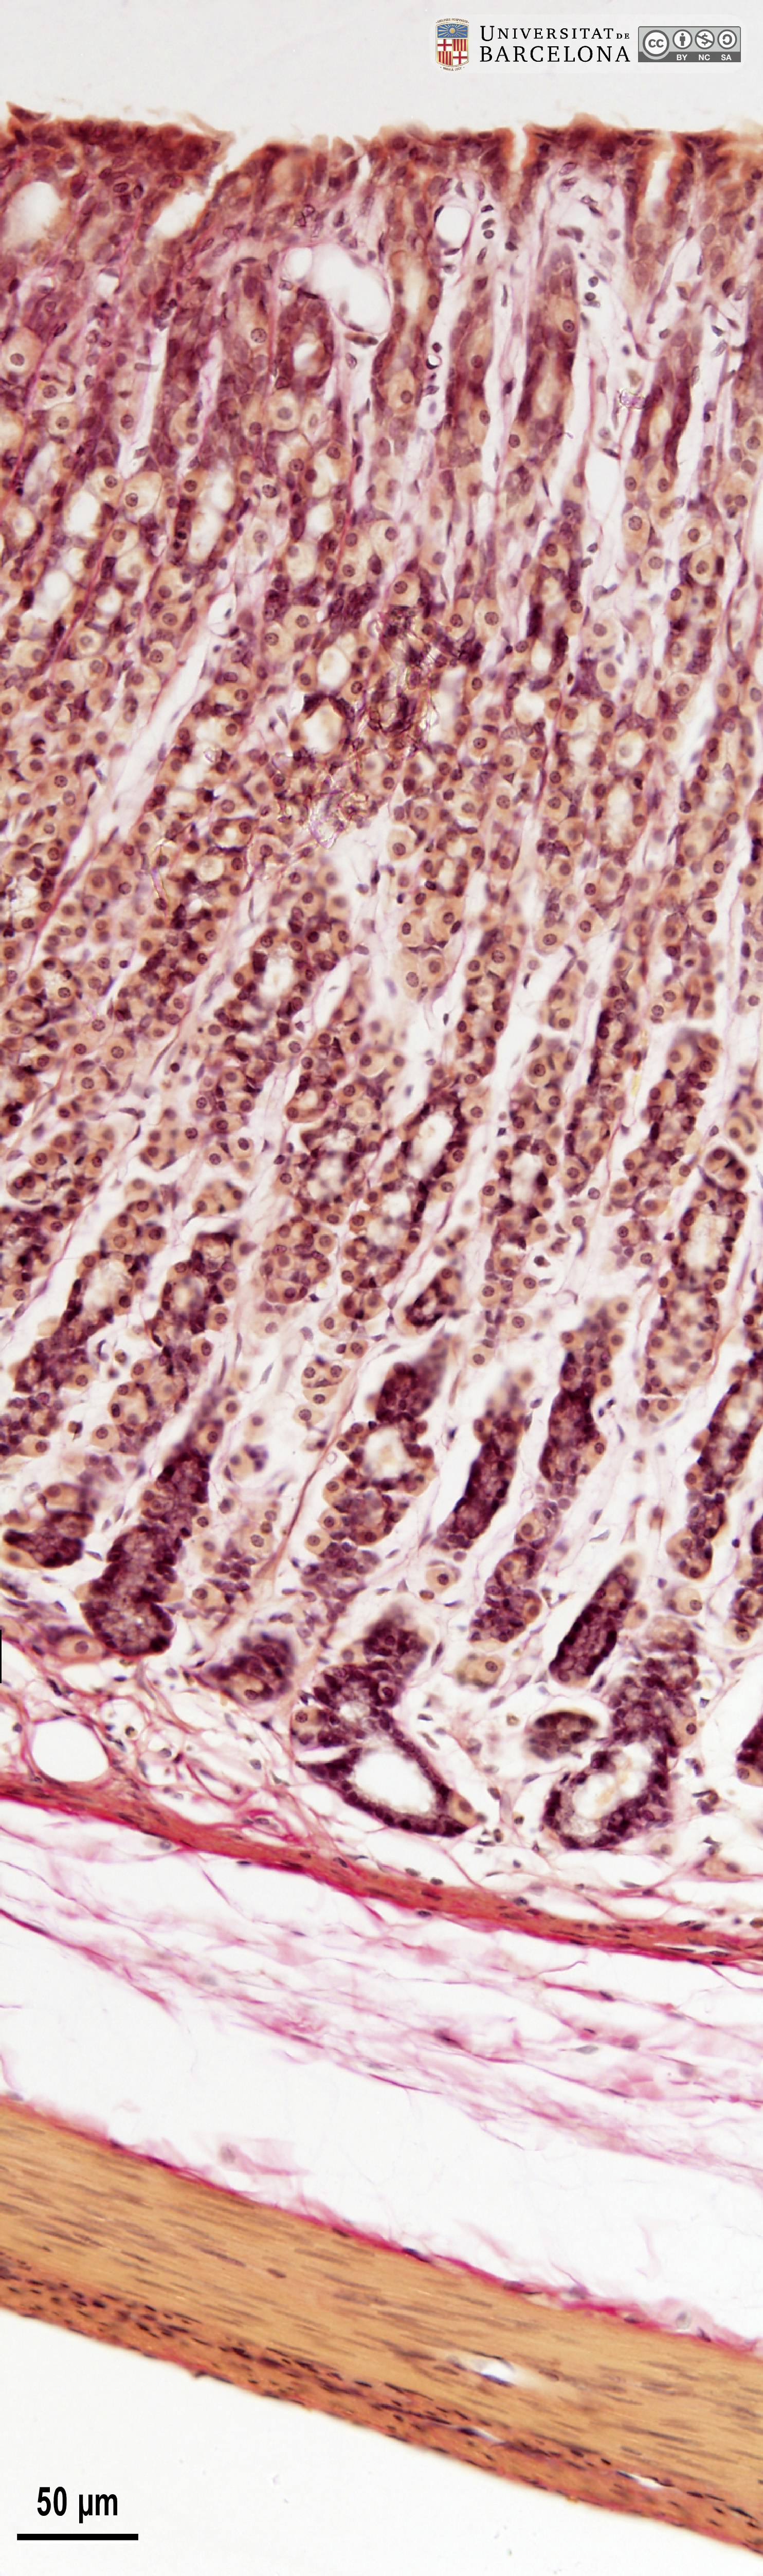

[ENG] A collection of micrographs illustrating the organisation of the stomach in rats. The layers of the gastric wall and their components –such as blood vessels, fibres and cell types– are shown in paraffin sections stained with hæmatoxylin-eosin stain or van Gieson trichrome. Semithin sections 2 µm thick were stained with toluidine blue. This collection complements the micrographs published by Dr Elena Sagristà i Mateo https://hdl.handle.net/2445/60213 — See also: https://diposit.ub.edu/dspace/browse?type=author&value=Sagrist%C3%A0+i+Mateo%2C+Elena

[CAT] Col·lecció de micrografies de l'organització de l'estómac de la rata. Es mostren les capes de la paret estomacal i els seus components (vasos sanguinis, fibres, tipus cel·lulars, etc.) en talls de parafina tenyits amb hematoxilina-eosina o el tricròmic de van Gieson i talls semifins de resina epoxi tenyits amb blau de toluïdina. Aquesta col·lecció complementa les micrografies publicades per la Dra. Elena Sagristà i Mateo https://hdl.handle.net/2445/60213 — I també: https://diposit.ub.edu/dspace/browse?type=author&value=Sagrist%C3%A0+i+Mateo%2C+Elena